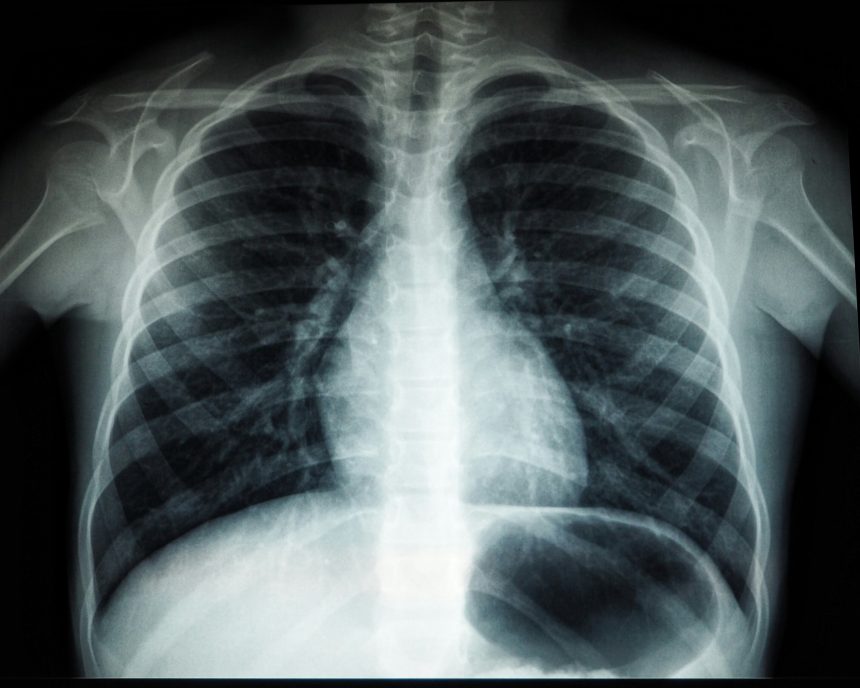

Lung cancer is a major cause of cancer-related deaths in the United States, yet only a small percentage of eligible individuals undergo recommended screening. Early detection through screening can significantly reduce the risk of lung cancer death, according to the National Cancer Institute. However, barriers such as identifying screening-eligible patients, limited awareness of screening recommendations, and time constraints during primary care visits have hindered screening efforts.